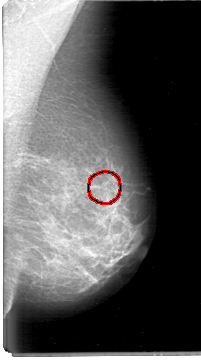

D_4054_1.RIGHT_MLO

LEFT_CC LINES 5326 PIXELS_PER_LINE 2971 BITS_PER_PIXEL 12 RESOLUTION 43.5 OVERLAY

FILE: D_4054_1.LEFT_CC.OVERLAY

TOTAL_ABNORMALITIES 1

ABNORMALITY 1

LESION_TYPE CALCIFICATION TYPE MILK_OF_CALCIUM DISTRIBUTION CLUSTERED

ASSESSMENT 0

SUBTLETY 3

PATHOLOGY BENIGN

TOTAL_OUTLINES 1

BOUNDARY